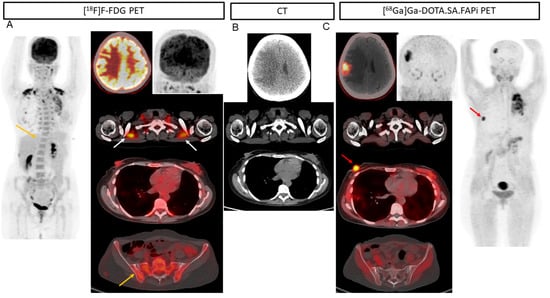

2. Results

2.2. Patient-Based Detection Rate Analysis

2.3. Lesion-Based Analysis

2.4. Comparison of Uptake and TBRs in Tumor Lesions